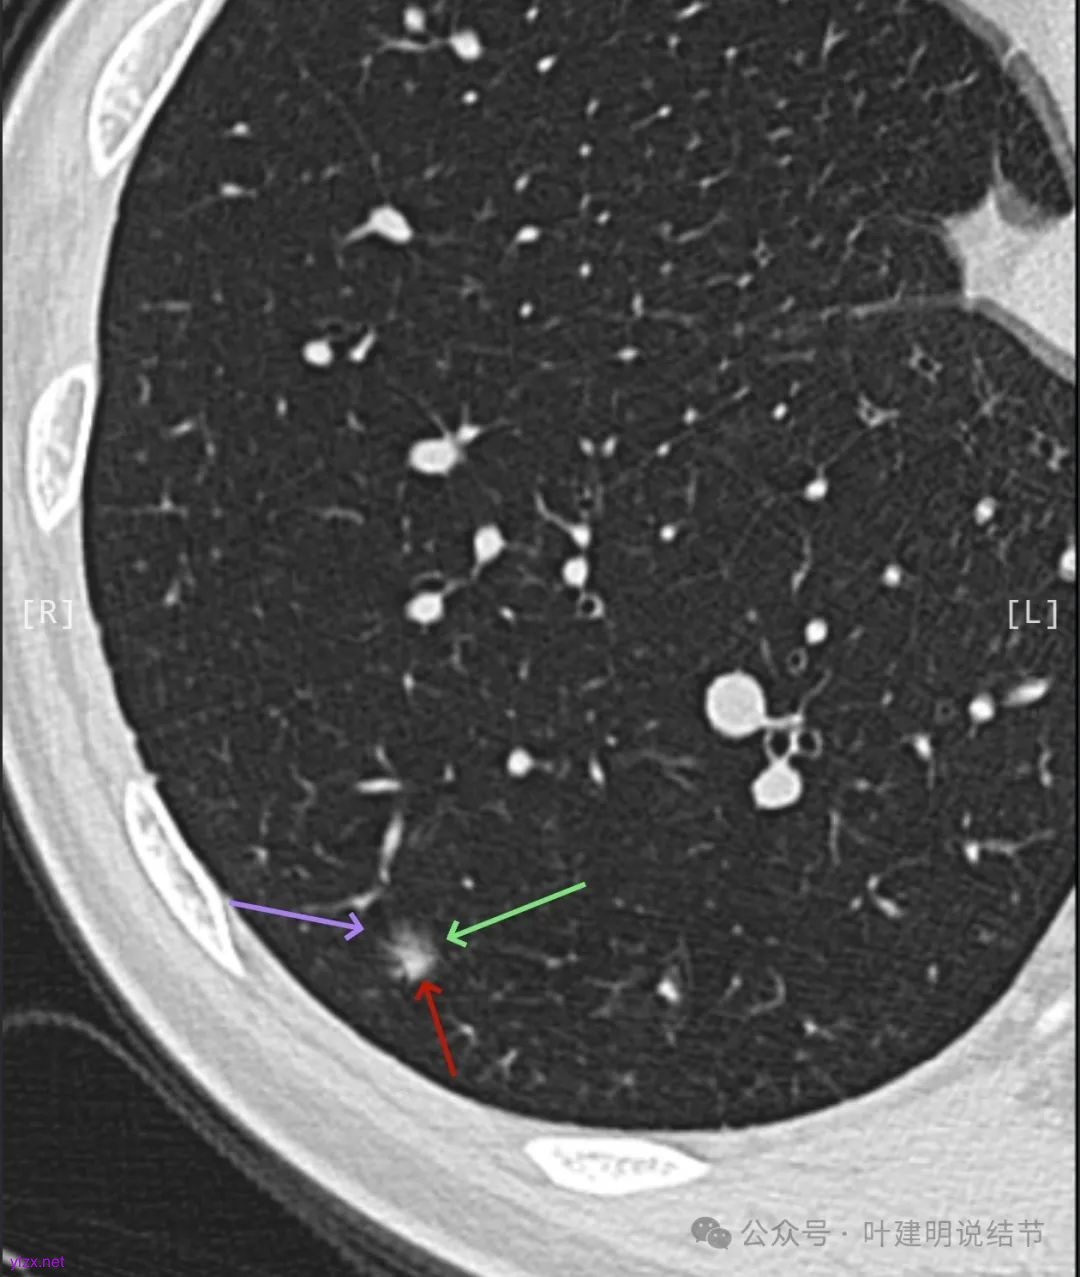

2024年9月时病灶较前有所增大,实性成分增大,表面不平,棘突明显,进入血管有异常增粗。

右下叶混合密度结节,随访略有进展,表面不平、边缘毛刺,有血管进入,整体轮廓与边界清,考虑是肿瘤范畴的,从进展缓慢来讲,恶性程度不高,应该是微浸润性腺癌或浸润性腺癌含贴壁与乳头型可能性大。由于位置好,能楔切,倾向考虑单孔胸腔镜下局部切了。意见供参考!

看了2017年的影像后,我又觉得病灶与附近炎性的形态类似,而且7年来进展也不厉害,慢性炎伴纤维增生的可能性也是有的。所以先半年复查,再有进展更像恶性再手术也可以。

逐层看了2024年的影像:

这个病例其实有反思回顾的价值,我想可以从中得出下面这些感想:1、混合磨玻璃结节随访持续存在且没有钙化或吸收好转,即使整体轮廓清,有血管征、有细支气管截断征、有毛刺与棘突征,且灶内密度杂乱,集齐许多恶性影像特征,仍不能下定论必为恶性;2、回头看病灶最终之所以不是恶性,而是慢性炎伴纤维增生与碳末沉积,最为关键的一是进展太慢,不符合混合密度结节含高密度实性成分的肺癌的生物学行为;二是实性部分密度过高而磨玻璃成分显得略偏模糊,看上去像有点晕征的味道。我反复总结过“混合密度实性成分过高而磨玻璃成分密度过低的容易是慢性炎或肉芽肿性炎伴纤维增生”。但临床的应用中仍不太敢下定论;3、多看几位医生也不能就100%明确。就如此例10位医生均考虑恶性范畴,虽有一位考虑原位癌,但其实也算是癌的范畴,但其实真正的影像上之所以判断的病灶部分不是肺癌,若牵强认为非典型增生与原位癌类似也可算浸润性病变,那也是碰巧而已,而不是从影像判断上看出有不典型增生,而密度高的却认定是良性成分;4、手术切除与否对于此例来说,仍是值得的,因为问了10位医生都说是肺癌,即使随访也压力巨大,而且密度不纯。从结果来看,已经存在非典型增生,继续随访,多年后也可能还是会发展成微浸润性腺癌或浸润性癌的可能性。而且楔切创伤不大,既明确诊断,也去除了病灶,是利大于弊的。当然这再次印证我一直坚持的原则:从风险高低来考虑手术与否以及干预的时机,而不要过于在意最后的病理结果。